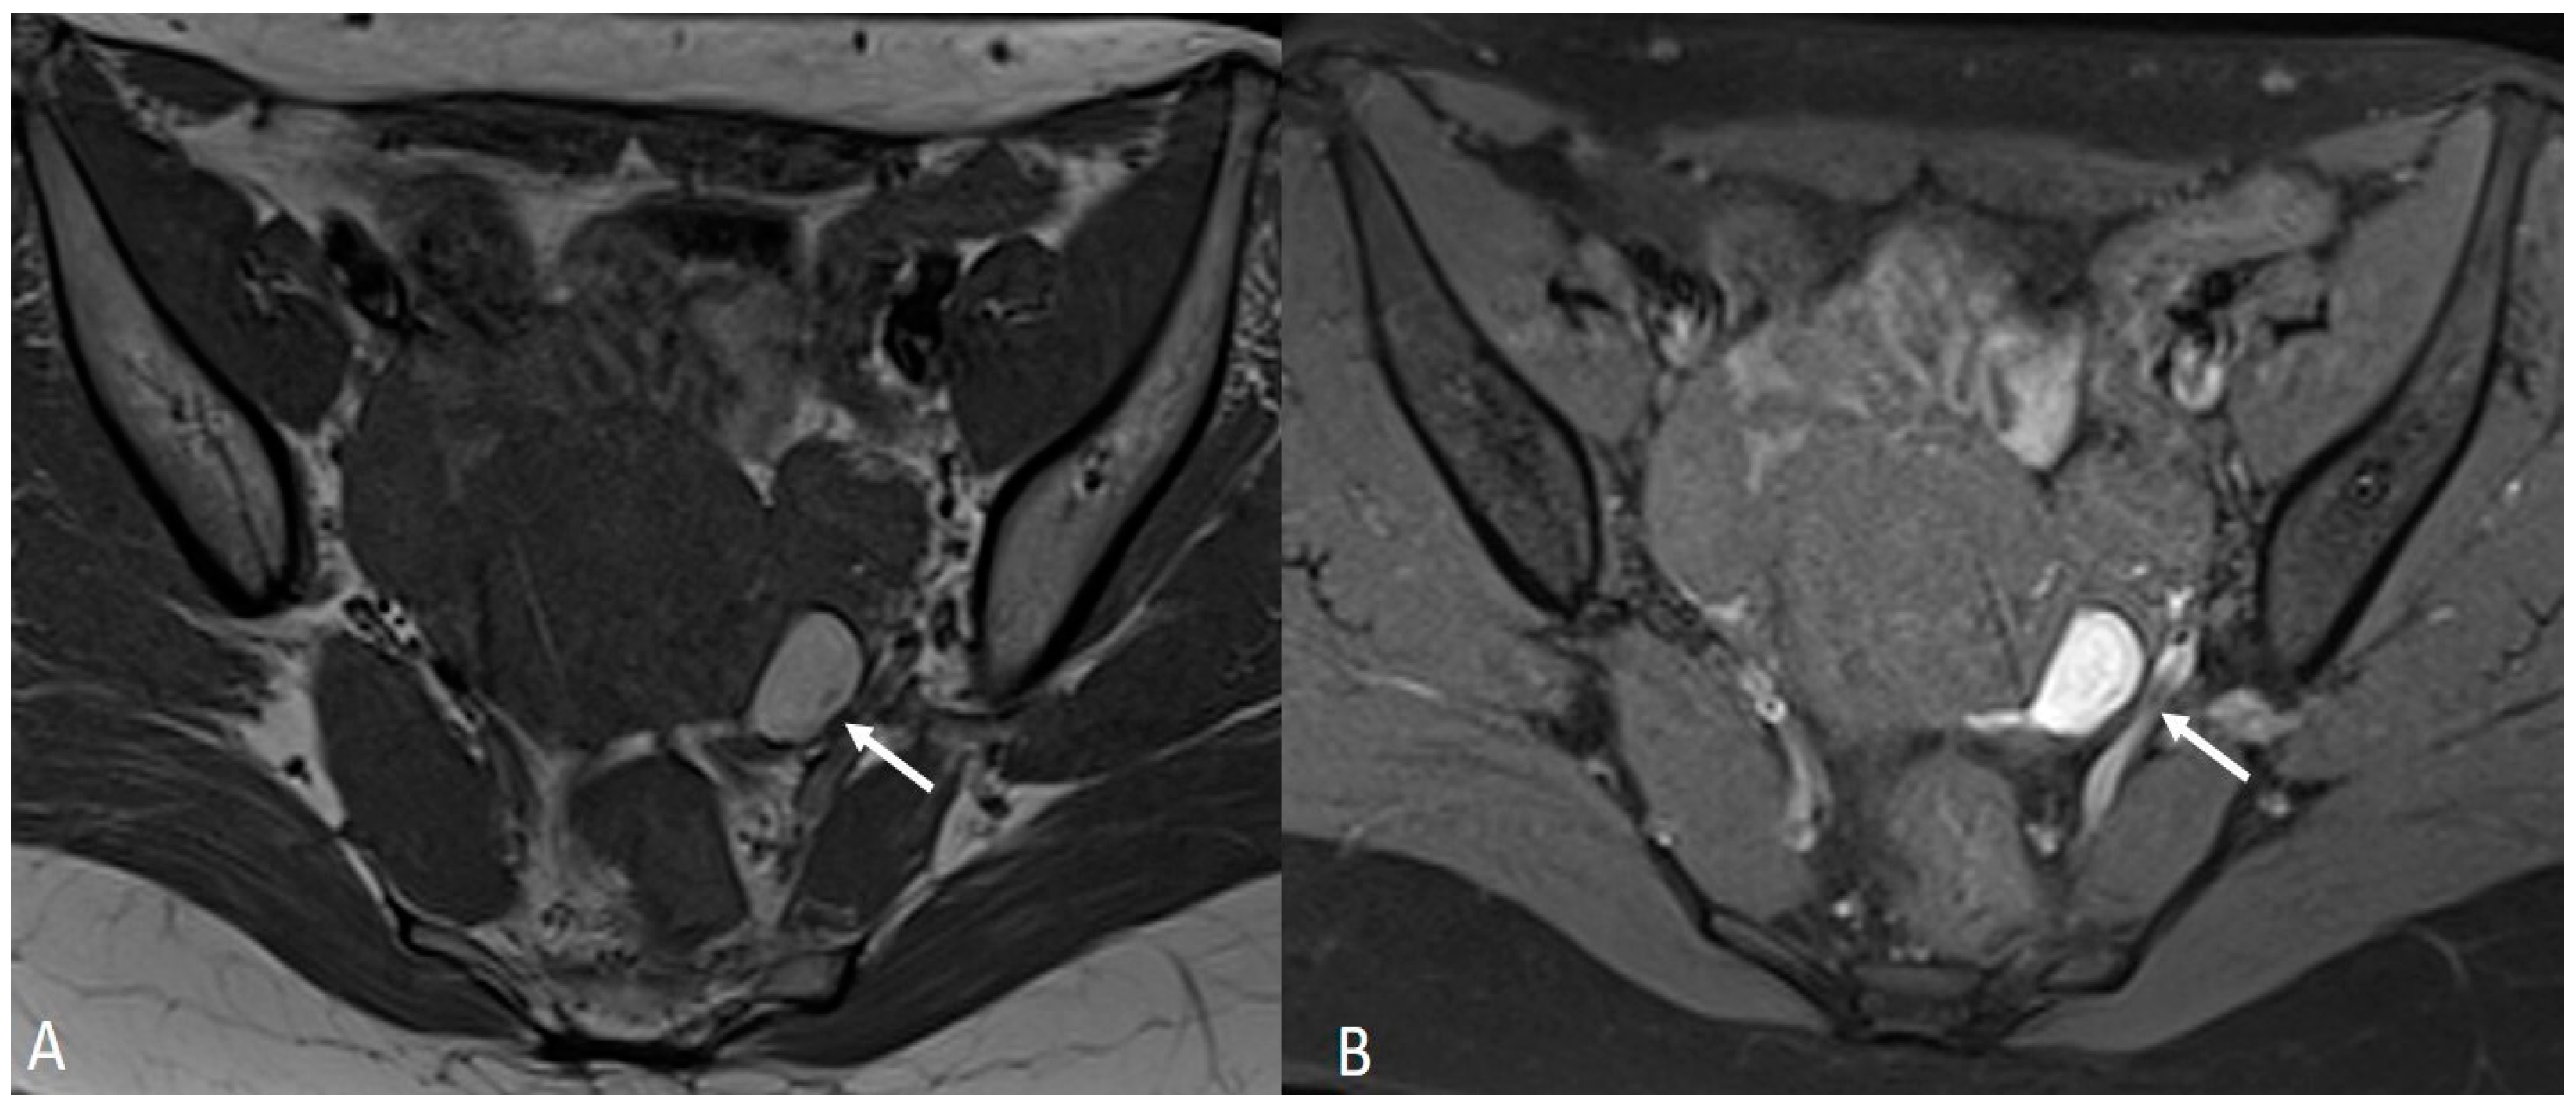

In other cases, the involvement of the round ligament can be appreciated as irregular contours with a nodular aspect [43] (Figure 2).

Figure 2.

Deep infiltrating endometriosis of the anterior and posterior compartments in 33-year-old female with dysmenorrhea, chronic pelvic pain, dyspareunia and dyschezia. (A) Sagittal T2WI. Evidence of external anterior adenomyosis and plaque of the vesico-uterine pouch (white arrow); (B) Sagittal T2WI. Retrocervical localization of DIE (white arrow); (C) Axial T2WI. Left uterosacral ligament (USL) localization (white arrowhead), plaque of vesico-uterine pouch (white arrow) with involvement of the round ligaments, particularly on the left (white dotted arrows), and adhesions with the ovaries (retraction of the broad ligaments).

Involvement of the proximal portion of ligaments (distance less than 2 cm from the cervix) may, in some cases, be associated with thickening at the level of the torus uterinus; in such cases, it is essential to report any mass or thickening in the upper portion of the posterior cervix, as this could cause the surgeon to proceed with a laparoscopic trans-vaginal approach [7] (Figure 2, Figure 3 and Figure 4).

Figure 3.

Right uterosacral ligament localization in a 43-year-old female. The right uterosacral ligament appears thickened at uterine insertion (white arrow).